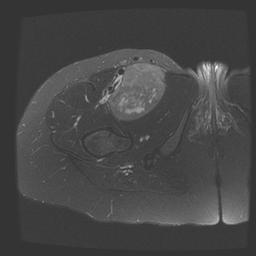

Leimyosarcoma Femoral Vein MRI Coronal T2Leimyosarcoma Femoral Vein MRI Axial T2